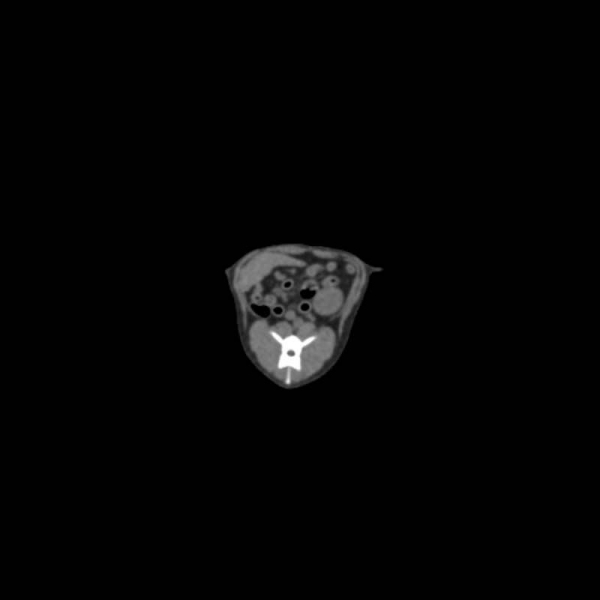

Fantom zagotavlja realistično simulacijo psa brez kontrastnega sredstva. Kosti in mehka tkiva so prikazana verodostojno z realističnimi vrednostmi CT za vsa tkiva pri 120 kVp napetosti cevi v CT. Zračni prostori so zapolnjeni s celuloznim polimernim kompozitom s približno -80 Hounsfieldovimi enotami.

Če se bo fantom uporabljal predvsem pri drugih napetostih cevi (npr. 100 kVp), se lahko po potrebi ustrezno prilagodi kalibracija vrednosti CT ? Fantom zagotavlja tudi realistične kontraste tkiv pri rentgenskem slikanju.